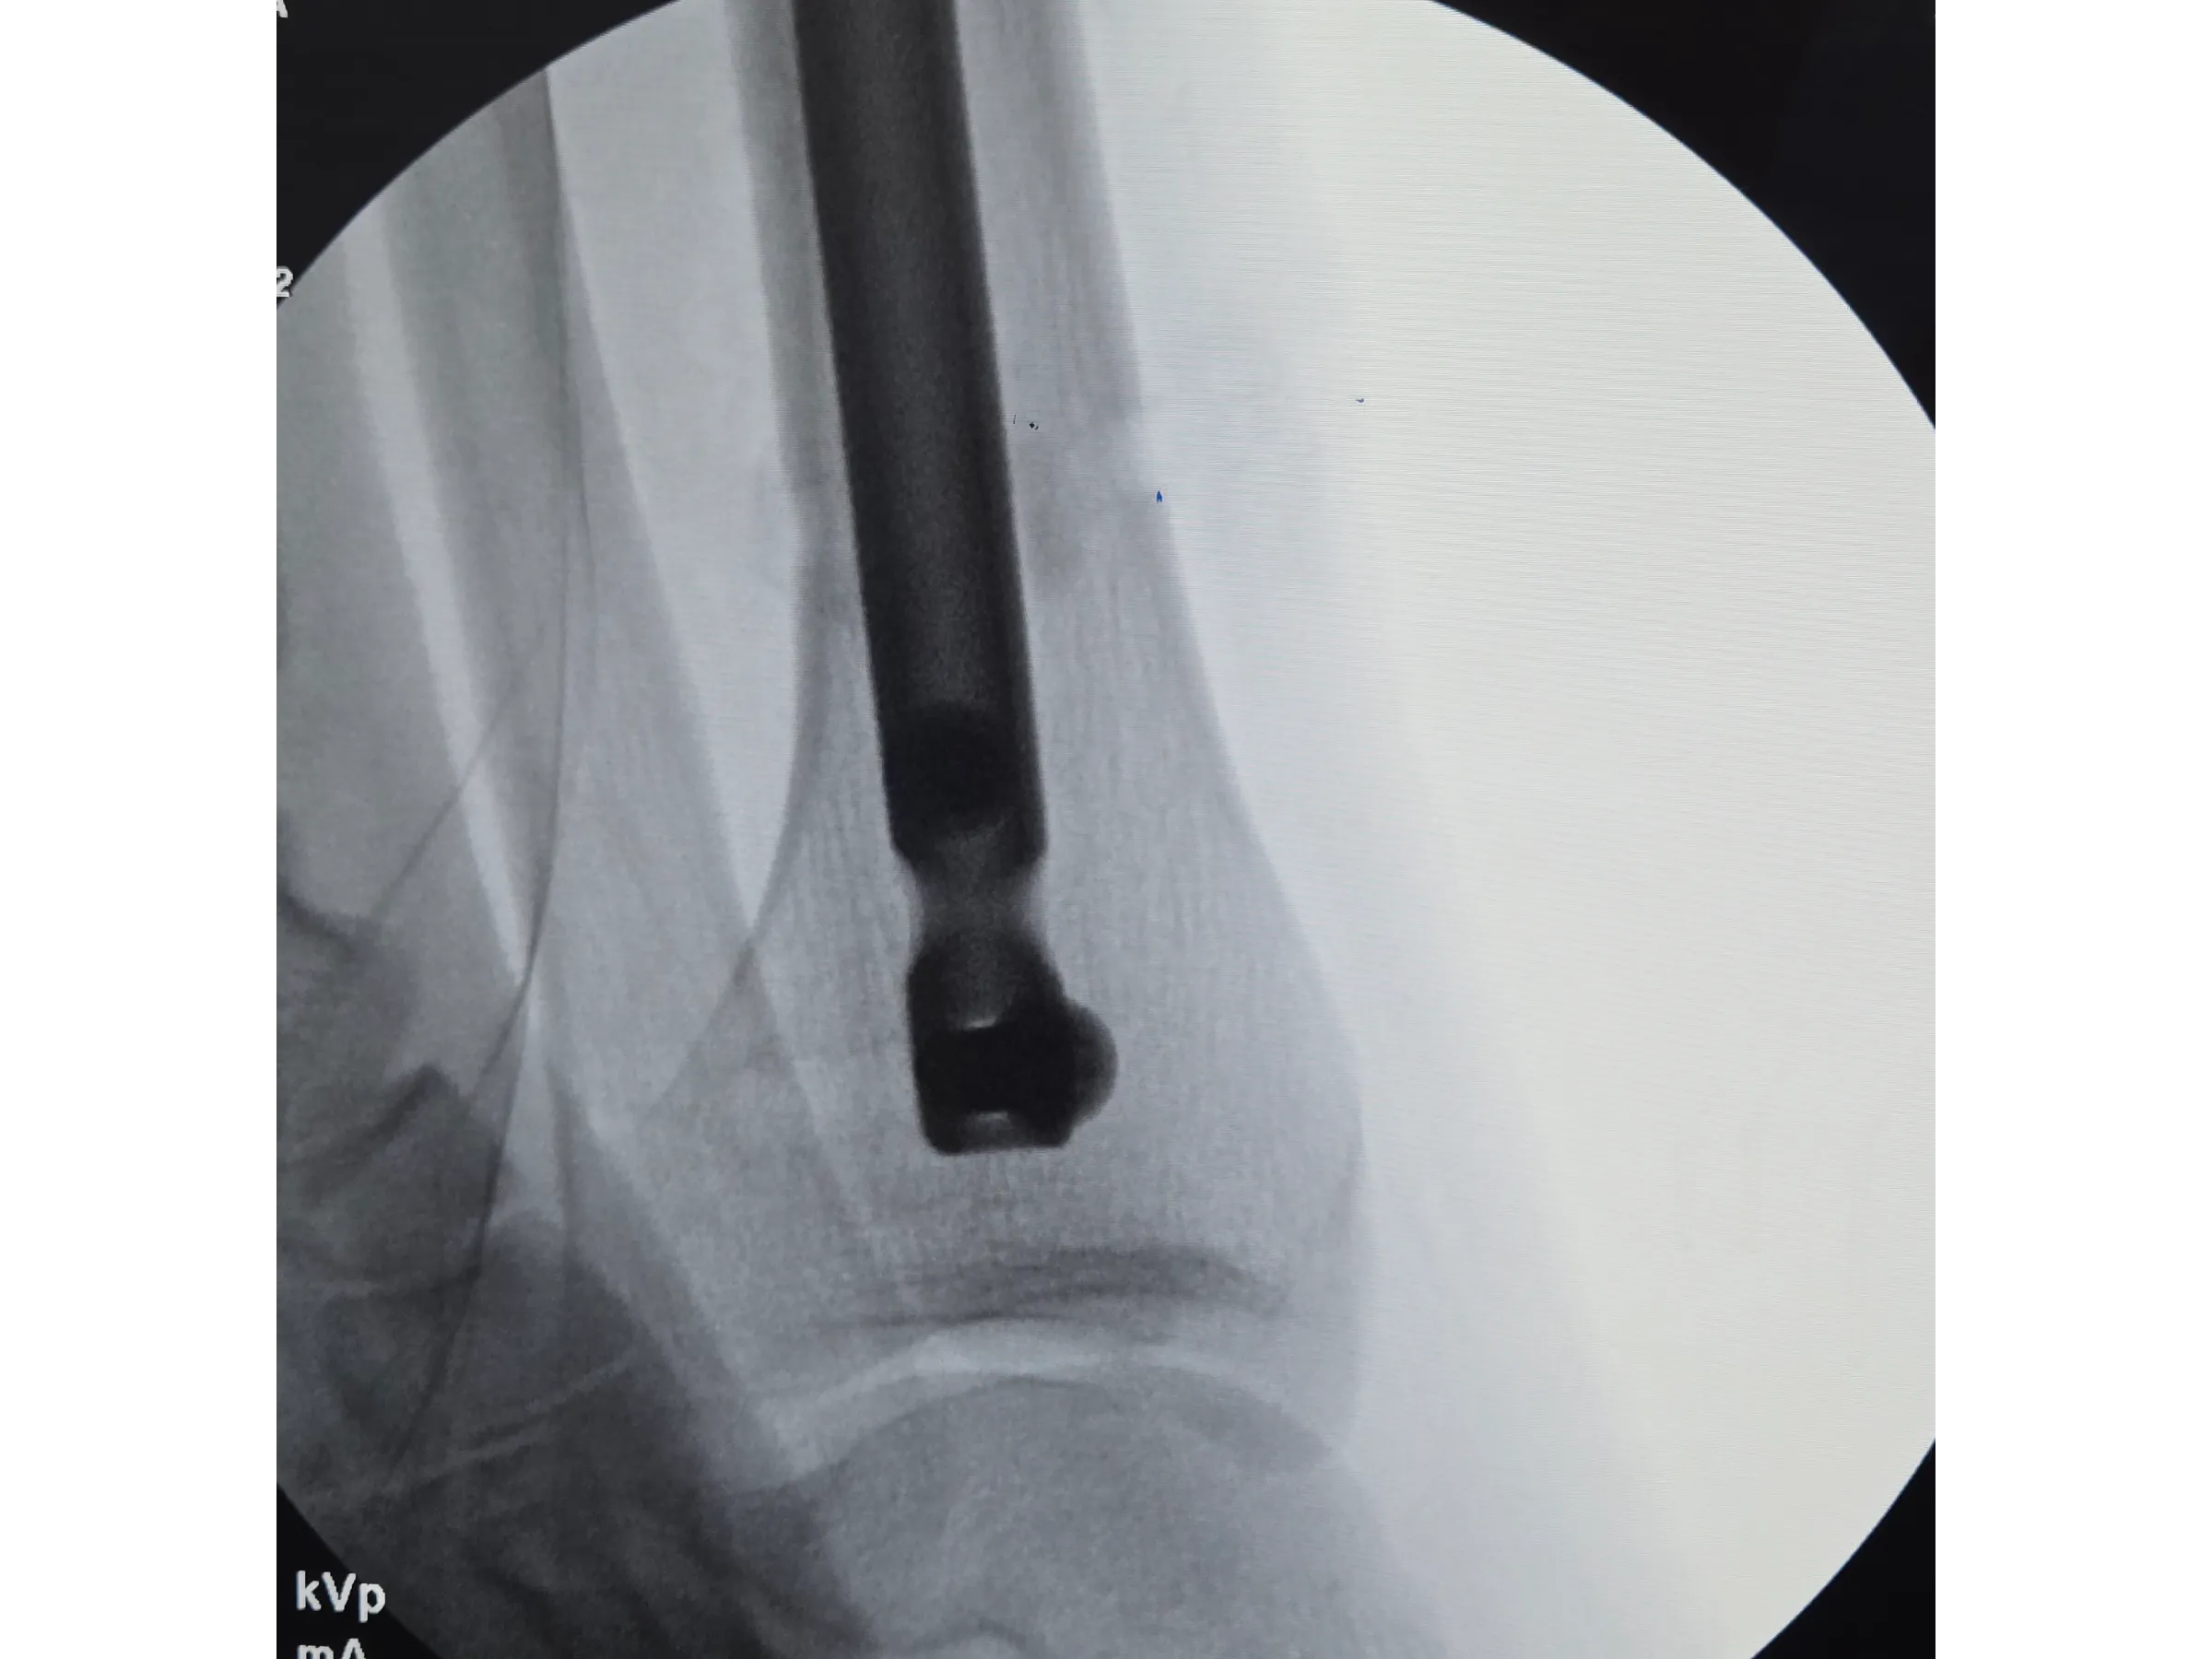

- Inserção da haste intramedular e checagem do posicionamento;

- Inserção da Haste com Estabilidade: Técnicas para evitar proeminência, garantir avanço adequado e minimizar trauma na retirada do fio olivado;

- Avaliação Pós-Implante: Critérios para confirmar estabilidade, alinhamento e ausência de proeminência da haste.